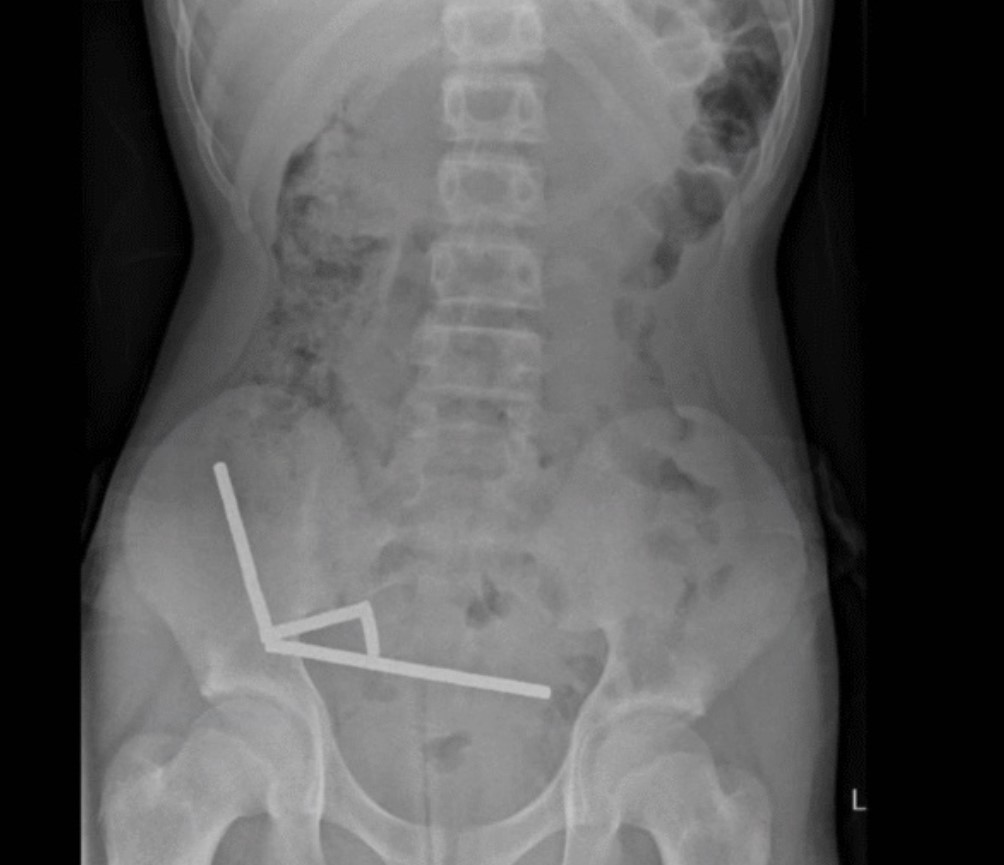

Рентгенівське зображення магнітів у черевній порожнині | Фото: ScienceAlert

Після того, як лікарі зробили рентгенівські знімки черевної порожнини підлітка, вони виявили, що в різних відділах кишківника хлопчика розташовані чотири лінійні ланцюжки з неодимових магнітів, які з'єдналися. Дрібні металеві предмети з'єдналися, створивши руйнівні наслідки.

Рентгенівський знімок, на якому видно ланцюжки магнітів у черевній порожнині новозеландського підлітка

Хірурги провели операцію і виявили, що магніти розташовані в різних відділах тонкої і сліпої кишки. З'єднуючись, магніти спричинили відмирання кількох ділянок тканини через нестачу крові. Тому хірургам довелося видалити частину кишківника хлопчика. Попри це підліток одужав і був виписаний з лікарні через вісім днів після операції.